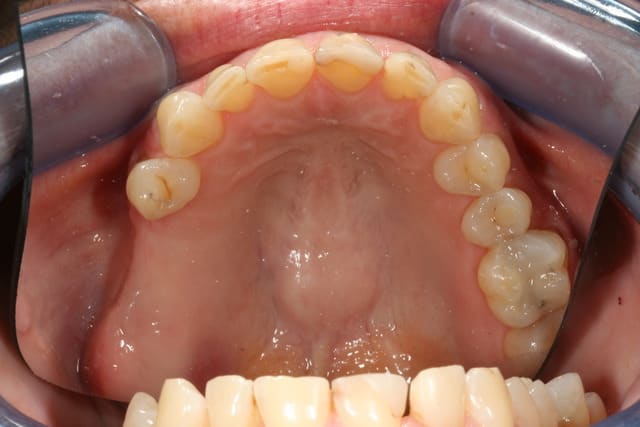

elle a eu gouttière en relation centrée un moment, puis avec l'amélioration des symptomes, (j'ai juste amélioré son calage je pense) on est passé au fixe, avec augmentation de la DV. Il y a eu implants 25 26 après sinus lift, couronne 36, bridge 45/47, onlay 16 et facettes palatines en composite de 13 à 23 et composites sur les incisives en bas

depuis ça va mieux, je suis juste déçu par l'articulé inversé de la 27 mais la position de l'implant ne permettait pas vraiment autre chose (encore qu'en jouant sur la couronne 36 et en vestibulant un peu les couronnes sur implant ça aurait peut être pu passer)

j'ai refait les compos des incisives avant de lancer tout ça, pour être sur du collage, et on aussi fait un éclaircissement.

Je suis assez d'accord pour la préparation supragingivale dans certains cas , être le moins invasif est l'axiome à retenir , inutile de s'enfoncer éperdument au risque de blesser le sulcus et l'attache .

Encore faut-il calculer son coup question teinte , et bien garder la même , l'application se fait alors pour des cas esthétiques de changement de forme des dents uniquement .

Une remarque, j'aurais fais au minimum de 14 à 24.

après le mock-up, j'avais proposé de faire 14 et 15 pour éviter un trop gros décalage avec la canine et faire un truc plus harmonieux

sur la coup ça lui disait bien, mais ça revenait quand même cher, donc on en est resté à 13-23